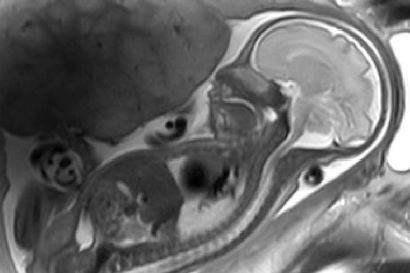

In a new study, published in Human Brain Mapping, a group of scientists, led by Dr Marcus Kaiser from the School of Medicine at the University of Nottingham, looked at epilepsy patients undergoing surgery.